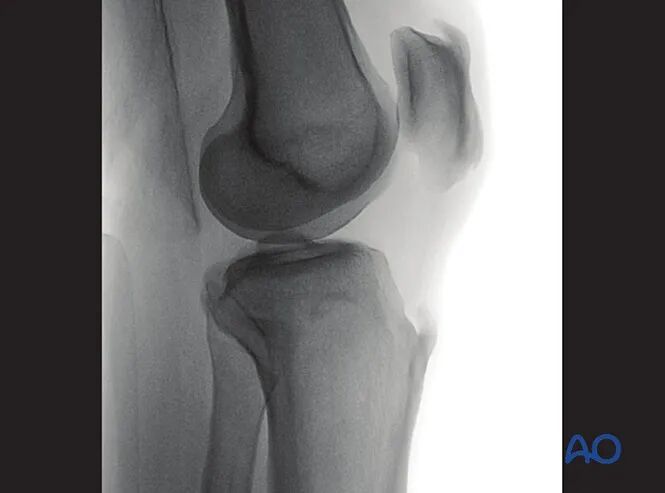

2. 胫骨近端前后位

最佳体位摆放要求

获取胫骨近端标准前后位影像需满足:

●患侧下肢完全伸直并处于中立旋转位;

●射线束与胫骨长轴垂直。

最佳影像的验证标准

满足以下条件即为胫骨近端最佳前后位影像:

●髌骨尖正对股骨髁间窝中心;

●腓骨头与胫骨近端外侧缘的重叠范围占腓骨头的1/4至1/3;

●射线束中心点对准胫骨平台。

可识别的解剖标志与线条

胫骨近端前后位影像中可清晰识别的解剖标志与线条包括:

1.外侧胫骨平台、

2.髌骨、

3.腓骨头、

4.内侧胫骨平台、

5.外侧胫骨棘、

6.内侧胫骨棘。

临床观察要点

该体位尤其适用于判断以下情况:

●关节内骨折复位不良(关节面台阶征);

●关节内植入物位置;

●内翻或外翻应力下关节间隙增宽(提示侧副韧带损伤);

●胫骨棘撕脱骨折(提示交叉韧带损伤);

●关节面与胫骨长轴的夹角是否正常(正常范围85°-90°)。

可拍摄健侧肢体影像作为对照参考。